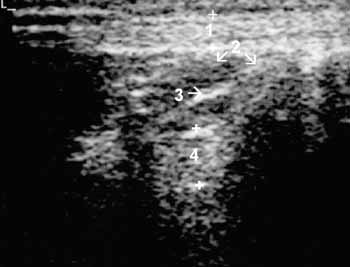

Рис. 4. Коленный сустав в норме. Поднадколенниковая область, сагиттальная

проекция; 1(+) — собственная связка надколенника, 2 — поднадколенниковое жировое

тело, 3 — поднадколенниковая синовиальнакя складка, 4(+) — передняя крестовидная

связка.